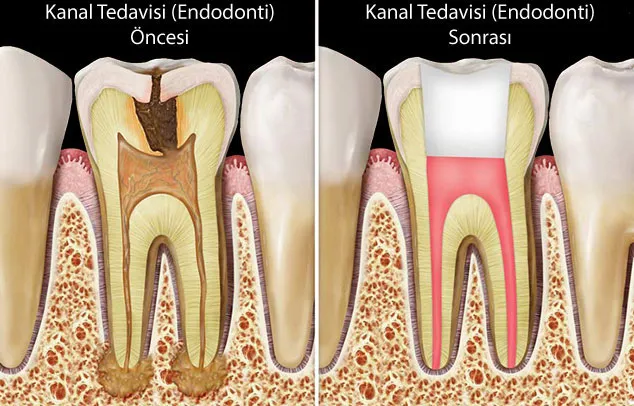

Kanal Tedavisi Mi, Diş Çekimi Mi?

Kanal Tedavisi

Kanal Tedavisi İşlemi

Kanal Tedavisi Sonrası Diş Ömrü